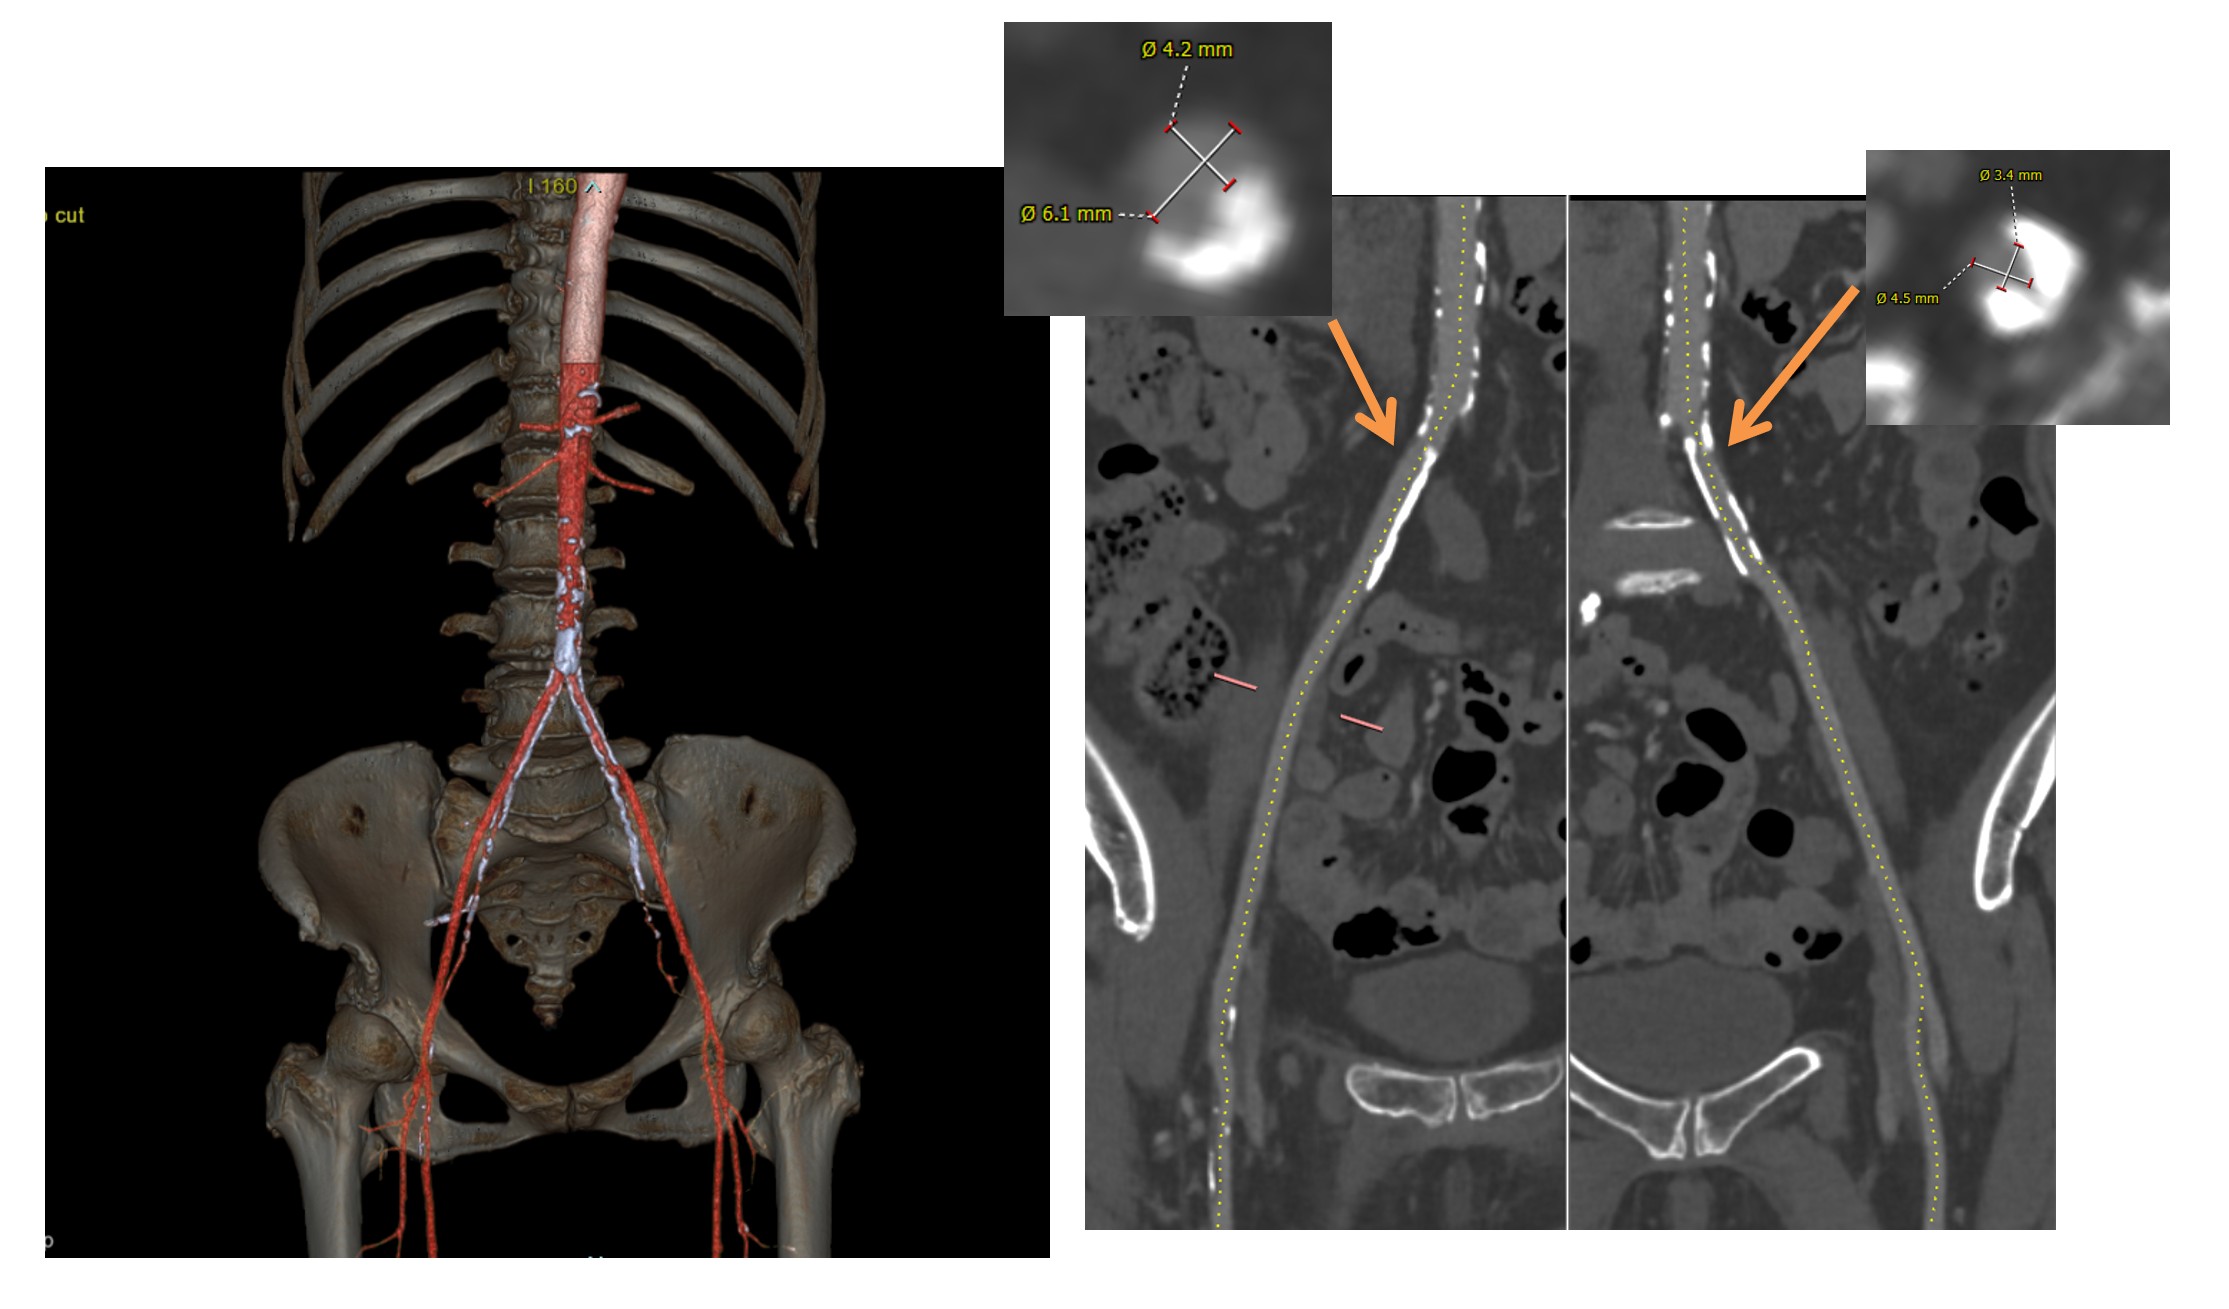

Relevant Test Results Prior to Catheterization

The procedure was performed under conscious sedation. A 14F eSheath+ was inserted via right femoral artery. The aortic valve was crossed using an AL 1.0 with an Argon straight wire, which was exchanged for SAFARI2 small. Although the diameter of iliofemoral artery was enough, delivery of SAPIEN 3 Ultra RESILIA 20 mm (S3UR) through the14F eSheath+ was challenging. The SAFARI2 wire was subsequently exchanged for a Confida Guidewire to get adequate support and back-up force; however, this also failed. Therefore, the 14F eSheath+ was pulled back to the common iliac artery, and the S3UR valve was advanced without the sheath to facilitate crossing through the narrowest segment of the iliofemoral artery. This maneuver succeeded to advance S3UR into abdominal aorta (Video 1). However, patient suddenly claimed severe abdominal pain and aortography revealed intimo-intimal intussusception, possibly caused during valve delivery (Video 2). Intravascular ultrasound (IVUS) also confirmed completely intussuscepted intima, and revealed absence of intimal layer at the terminal aorta. The TAVR procedure was subsequently aborted. The resultant tubular structure of completely detached intima posed a risk of antegrade or retrograde migration, potentially leading to acute aortic occlusion. Therefore, an endoprosthesis (GORE EXCLUDER) was implanted in the infrarenal aorta to stabilize the lesion (Video 3).